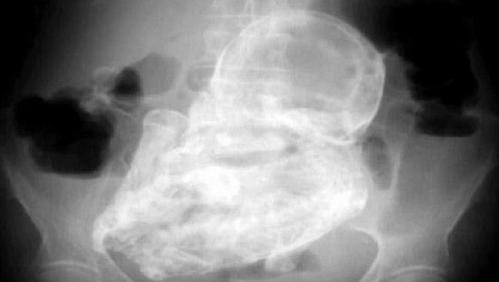

Bạn đã nghe nói về hiện tượng y học hiếm gặp được gọi là lithopedion (mang thai đá), trong đó thai nhi ch:ết trong bụng mẹ và bị vôi hóa theo thời gian chưa? Mới đây, tài khoản X Non Aesthetic Things, với 4,8 triệu người theo dõi trên nền tảng này, đã chia sẻ "ảnh chụp CT của một thai nhi bị vôi hóa" và cho biết tình trạng này đã tồn tại khoảng 30 năm.

Theo Hindustantimes, dòng trạng thái của Non Aesthetic Things bên cạnh ảnh chụp CT có nội dung: "Ảnh chụp CT này là của một phụ nữ 73 tuổi, người mà các bác sĩ đã phát hiện ra một b:ào thai bị vôi hóa 30 năm tuổi".

Một người khác viết: "Hình ảnh chụp CT cho thấy khoảnh khắc các bác sĩ phát hiện một 'em bé đá' trong t:ử c:ung của một phụ nữ 73 tuổi đến từ Algeria. Em bé đá, còn được gọi là thai lưu. Khi thai kỳ không phát triển, cơ thể không có cơ chế tự nhiên để đào thải thai nhi ra ngoài. Kết quả là, cơ thể trải qua quá trình vôi hóa, về cơ bản biến b:ào thai thành 'đá'".